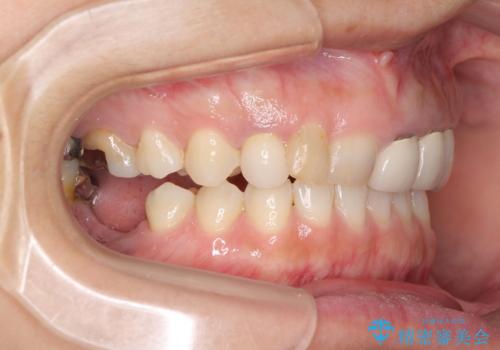

そのため右下の奥歯に強い負担が生じていて、むし歯が大きかったこともあり、抜歯が必要な状態でした。

また、右下の抜歯が必要な奥歯は、矯正治療の途中でインプラントを埋入し、矯正治療後に上顎と合わせて補綴治療を行うこととしました。